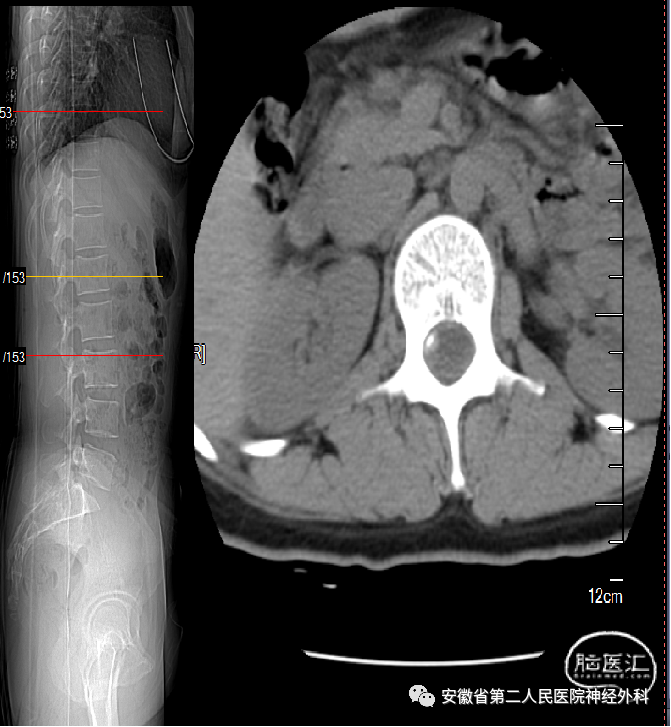

术前CT